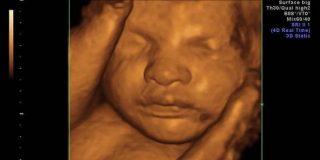

ΠερισσότεραΥπερηχογράφημα – Μαιευτικοί υπέρηχοι στην εγκυμοσύνη

Μαιευτικοί υπέρηχοι στην εγκυμοσύνη. Προγεννητικός έλεγχος για το μωρό, Υπέρηχος 4D, Αμνιοκέντηση, CVS, Β επιπέδου, υπερηχογράφημα ανάπτυξης & Doppler.